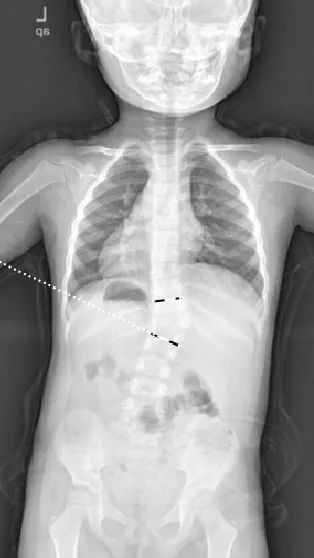

▲ 女,3岁4个月,先天性脊柱侧弯半椎体畸形

▲ 女,7岁,先天性脊柱侧弯半椎体畸形